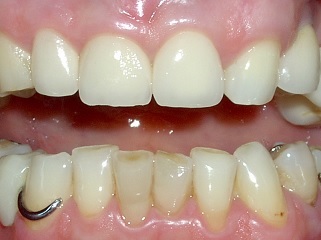

IL TUO DENTISTA VEDE ABBASTANZA?

Pare che Galileo ci vedesse bene ma pensate che avrebbe potuto studiare il sistema solare altrettanto bene senza l'aiuto del suo telescopio?

La larghezza reale di uno degli incisivi che vedi in foto è di circa 8 millimetri, all'interno di esso sono contenute strutture microanatomiche complesse che il tuo dentista deve vedere per poterle rispettare.

Pensi che sia più facile fare un buon lavoro vedendo con un ingrandimento 5 volte superiore?

Come puoi vedere nell'ingrandimento, tra i due incisivi è presente un notevole quantitativo di placca che non risulta visibile ad ingrandimento normale.

I tuoi denti sono preziosi, assicurati che vengano utilizzate tutte le tecnologie disponibili per salvaguardarli!